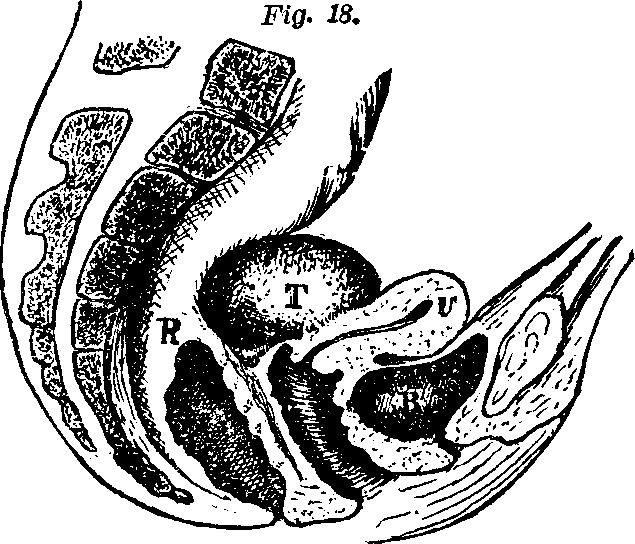

Fig. 18. Anatomy of knee joint. 1. Lower

end of thigh-bone. 3. Knee-pan. 2, 4 Ligaments of the

knee-pan. 5. Upper end of the tibia, or shin-bone. 6, 12.

Cartilages.